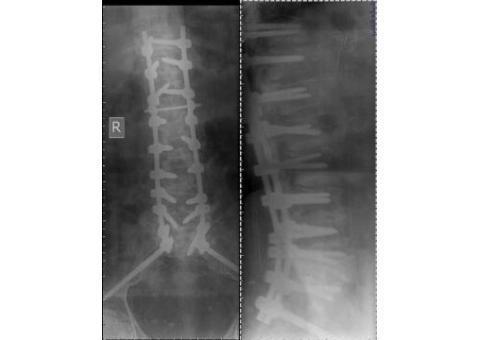

ارایه ی خدمات رادیولوژی و سونوگرافی در منزل به صورت شبانه روزی و بدون تعطیلی در کلیه ی نقاط کشور . تیم تصویر برداری گروه پزشکی امید متشکل از بهترین پزشکان و کارشناسان فارغ التحصیل از دانشگاه های برتر کشور هستند. امروزه با توجه به ترافیک سرسام اور به ویژه در کلانشهرها و همچنین شیوع ویروس کرونا و همچنین هزینه های بالای امبولانس هم از نظر اقتصادی و هم از نظر صرفه جویی در زمان و از همه مهمتر برای پیشگیری از ابتلای به بیماری کرونا، استفاده و بهرمند شدن از خدمات پزشکی و تصویر برداری پرتابل در منزل بیش از پیش همه گیر شده است. و تیم پزشکی امید مفتخر است که با ۱۴سال سابقه در ارایه ی خدمات رادیولوژی پرتابل در منزل و بکارگیری متخصصین بنام کشور و استفاده از بروزترین تجهیزات قابل حمل، در این ایام که پاندمی کرونا نفس سلامتی را تهدید میکند، در کنار هم میهنان عزیز بتواند گرهی از کار خانواده هایی که بیمار در منزل دارند را باز کند. کافیست با ما تماس بگیرید،۰۹۳۹۹۵۴۵۰۸۸ - ۰۹۱۰۵۵۴۵۷۹۰ - ۰۲۱۹۱۰۱۶۹۲۳